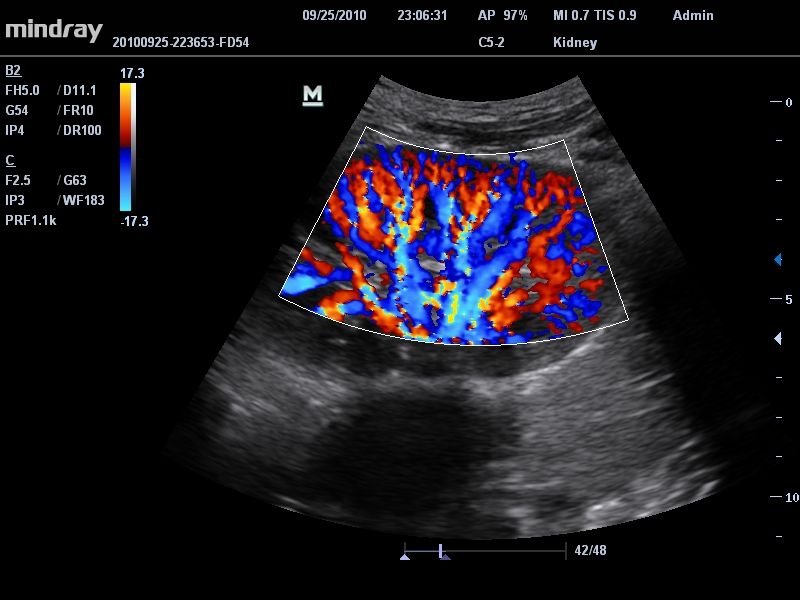

Цветовой допплер:

Да

Энергетический допплер:

• Режимы сканирования: B/M/CFM/PDI/Направленный PDI/PW, HPRF, Тканевая гармоника, М- и цветной М-режим.